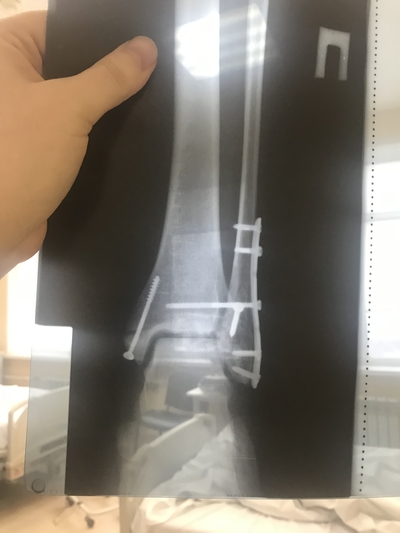

Случилась у меня такая беда. Двухлодыжечный перелом с отрывом задней берцовой кости и подвывихом кнаружи, именуемый ещё трехлодыжечным. Это было 31 декабря. В январе мне поставили пластину и позиционные винты. В марте сняли гипс, две недели назад я перешла с костылей на трость, благодаря курсу массажа. До этого пыталась - было больно. Сейчас хожу с тростью. По квартире на пару-тройку метров могу пройтись на своих двоих. Спокойно вожу автомобиль, хоть где-то эта нога неудобств не доставляет. Скоро предстоит снятие винтов, а через полгода - пластины. Я хромаю.

Это после операции.

На следующий день на контрольный рентген

На большой берцовой кости отломил полностью отросток (после вытяжки видел на снимке, он был в 1см от кости), на Малой косой облом на несколько см.

прикрутили пластину и установили болты.

Сегодня все выглядит вот так.

Теперь 2 месяца не наступать на ногу, ходить в лангете, затем снимать болты и разрабатывать ногу. И ещё несколько месяцев с тростью. Пластину снимут через год.